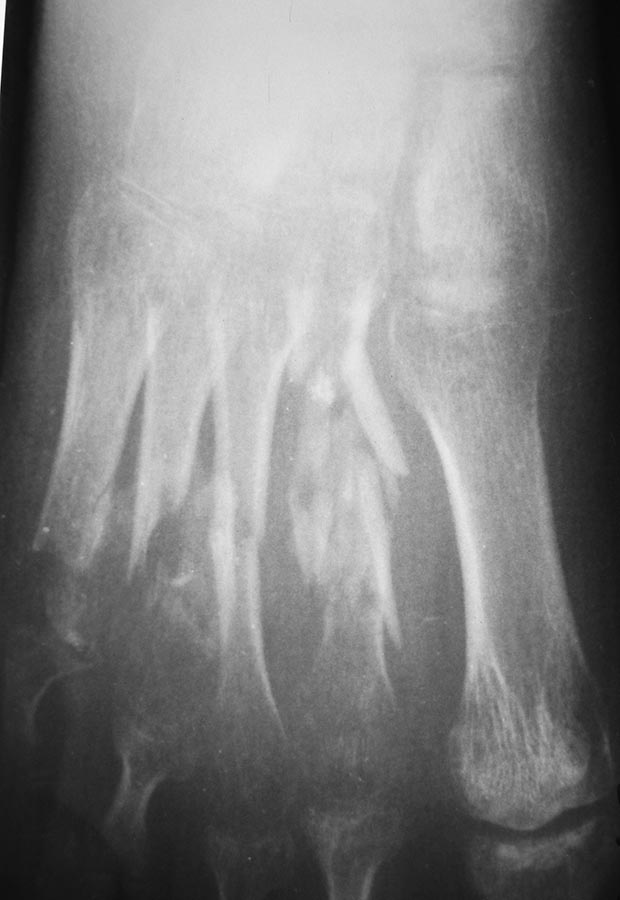

Пациентка 19 лет 11.05.13 получила травму в результате ДТП. диагноз:

Открытые 3а степени оскольчатые переломы диафиза 2-5 плюсневых костей,

перелом проксимальной фаланги 5 пальца, разрыв сухожилия разгибателя 4

пальца правой стопы. При поступлении выполнено ПХО открытых переломов,

фиксация спицами. Рана тыла стопы заживала без воспаления, однако

имелся частичный некроз кожного лоскута. По снятии швов произведена

иммобилизация циркулярной повязкой. Снимки стопы через 2,5 мес.

иммобилизации.